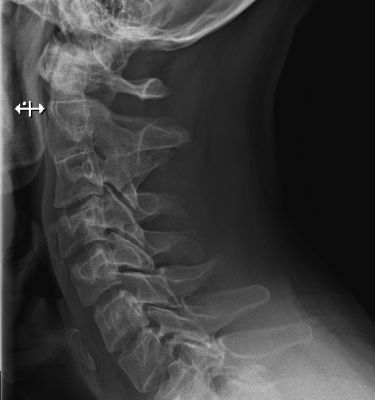

Кривошея на рентгене.

Диагностика

Для выявления деформации костных структур при остеохондрозе, полиостеоартрозе, спондилезе наиболее информативна рентгенография. Деструктивно-дегенеративные изменения хрящевых тканей, в том числе межпозвоночных грыж, а также связочно-сухожильного аппарата обнаруживают с помощью УЗИ, МРТ, КТ.